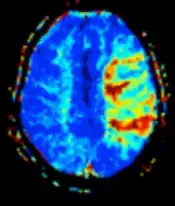

| Perfusion weighted (PWI) | Dynamic susceptibility contrast | DSC | Measures changes over time in susceptibility-induced signal loss due to gadolinium contrast injection.[72] |

|